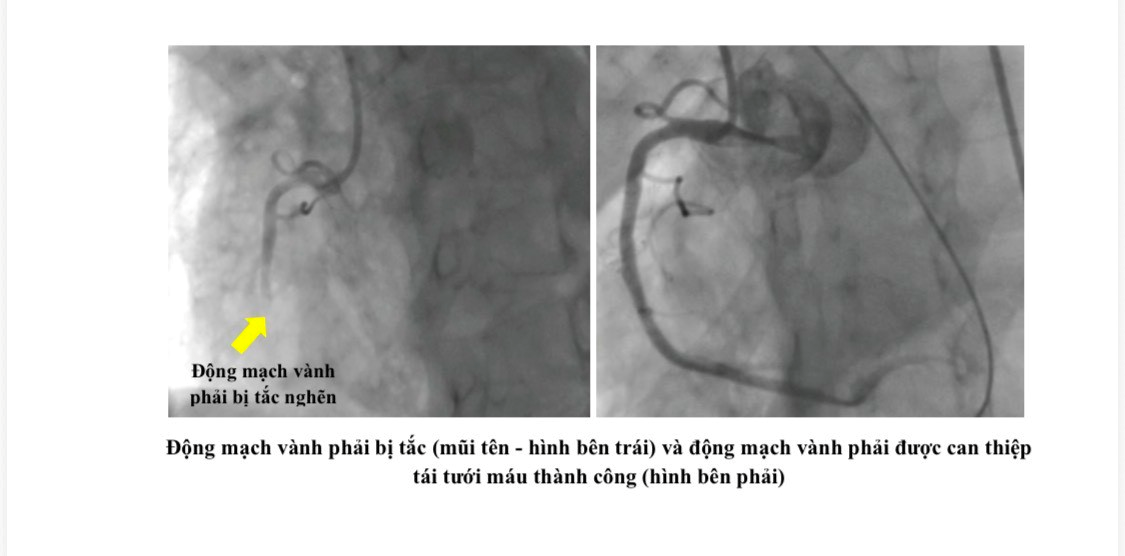

Ngay khi hệ thống tuần hoàn và tri giác của bệnh nhân có dấu hiệu hồi phục, các bác sĩ của 2 bệnh viện đã phối hợp vận chuyển người bệnh về Bệnh viện Nhân dân Gia Định để tiếp tục được hồi sức chuyên sâu. Tại đây, bệnh nhân được chụp mạch vành khẩn cấp và phát hiện có nhiều huyết khối gây tắc động mạch vành phải – là nguyên nhân chính gây ngưng tim trước nhập viện. Các bác sĩ Khoa Hồi sức tim mạch của Bệnh viện Nhân dân Gia Định đã nhanh chóng đặt stent mạch vành và tiếp tục duy trì tuần hoàn ngoài cơ thể cho bệnh nhân. Hiện tại, bệnh nhân tỉnh táo, tiếp tục được theo hồi sức và dõi sát tại Khoa Hồi sức tim mạch.